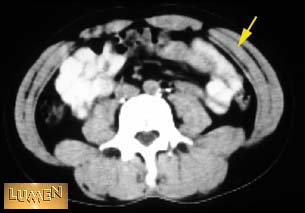

Question: Identify.

Answer

Internal abdominal oblique m.